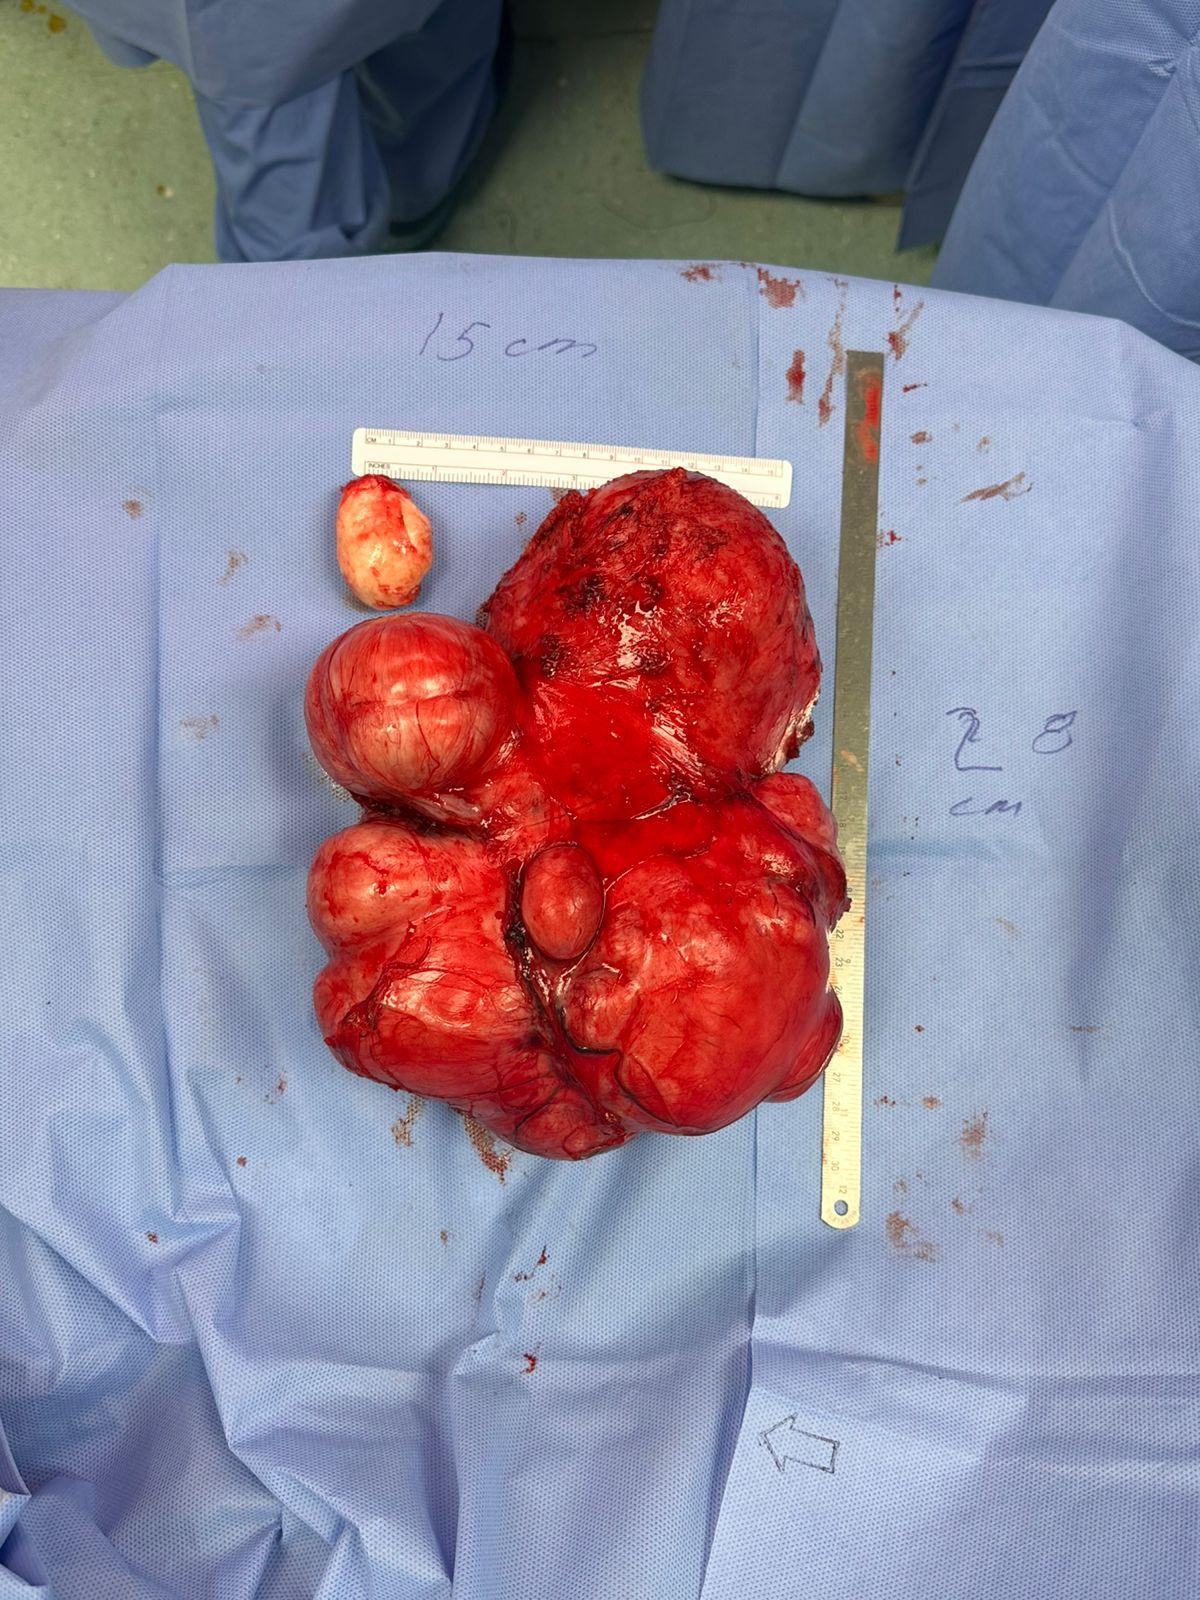

نجح فريق طبي في مدينة الملك عبدالله الطبية، عضو تجمع مكة المكرمة الصحي، في إجراء عملية جراحية دقيقة لاستئصال ورم بحجم جنين بحجم 30×15 سم من سيدة سعودية في العقد الثالث من العمر.

وأشار: إلى أن الفريق الطبي قام بالتحضيرات للعملية شملت إجراء فحوصات مخبرية وأشعة دقيقة، بالإضافة إلى معاينة شاملة من قبل قسم التخدير لضمان أعلى معايير السلامة الطبية. وبعد تخطيط دقيق، تم إجراء العملية عبر فتح البطن واستئصال الورم بالكامل مع الحفاظ على الرحم والمبيضين، حيث استغرقت العملية ثلاث ساعات تكللت بالنجاح ولله الحمد.

وبين التجمع الصحي: أن المريضة تم تنويمها بعد العملية في قسم التنويم لمدة ثلاثة أيام تحت المراقبة الطبية الدقيقة، حيث أظهرت تحسنًا ملحوظًا في حالتها الصحية. وخرجت المريضة من المستشفى في اليوم الرابع بعد استعادة عافيتها بشكل كامل.